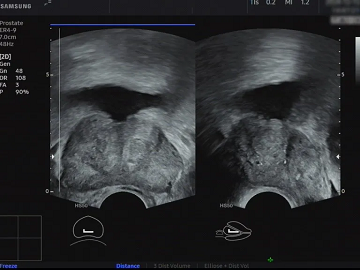

前列腺超声(排尿信号):直观地观察前列腺的大小、形状和增生结节,结合残余尿液测定,为尿频和排尿困难提供准确的诊断。

.png)